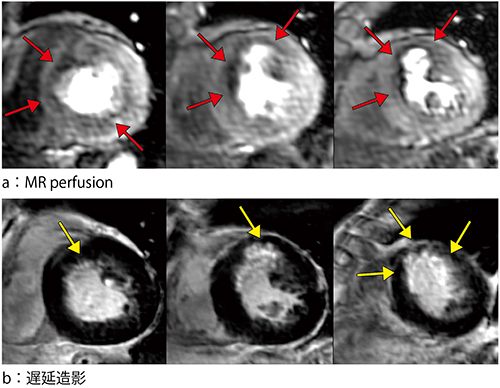

図4 治療前MR画像

左から心基部,心中部,心尖部。前壁中隔に内膜側優位の心筋血流低下があり(→),内膜側に遅延造影を認める(→)。